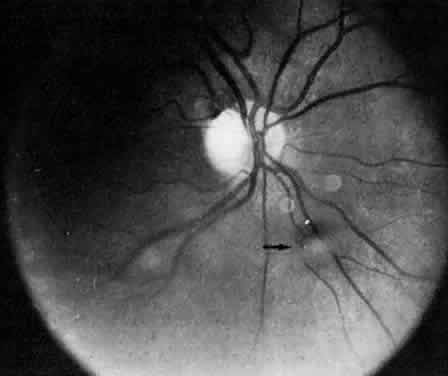

CLINICAL COURSE The clinical course is marked by chronic low-grade inflammation, which may be punctuated by episodes of exacerbation. In a study of 100 patients, Smith and colleagues13 divided the clinical course of their patients into three categories. The first group (10% of the eyes) followed a benign self-limiting course of gradual clinical improvement without episodes of exacerbation. The second group (59% of the eyes) followed a smoldering, prolonged course without episodes of exacerbation. The third group (31% of the eyes) followed a smoldering and prolonged course with episodes of exacerbation. About 4% of their cases underwent spontaneous remission. In pars planitis, the severity of the disease has no correlation to the duration of disease. Cases that are unilateral at first presentation may become bilateral later. Pars planitis is bilateral about 71% to 75% of the time.4,13,19 Often there is asymmetry in severity between eyes. In our experience, unilateral cases tend to have a milder course than bilateral cases. The presence of snowbank may indicate more severe and prolonged vitreous inflammation and often is associated with cystoid macular edema.30 In most of the patients, the clinical course becomes milder with time, and it usually enters remission between the patient's midthirties and early forties. HISTOPATHOLOGY Few pathologic reports of pars planitis have been described. Most cases are long-standing and chronic. Early changes have not been reported. Histologically, the snowbank is composed of glial elements, type VI collagen, and laminin.31 Extensive fibroglial proliferation and fibrous astrocyticlike cells have been seen in the vitreous base.32,33 These cells can synthesize basement membranes and produce large-diameter collagen fibrils.32,33 Fibrovascular tissue may be present in the snowbank and consists of well-differentiated capillaries that probably originate from the peripheral retina.33 The vitreous is usually collapsed and detached posteriorly from the retina. Multinucleated giant cells and epithelioid cells have been demonstrated in the vitreous snowballs.34 There is cellular proliferation from the retina and hyperplasia of the nonpigmented ciliary epithelium.34 The choroid usually does not show significant inflammation.31,34 Lymphocytic cuffing and mural infiltration of the retinal venules can be present, consistent with periphlebitis and phlebitis, respectively.33 The retinal arterioles are spared.33 These lymphocytes are mostly T-helper cells.31 Histologic changes consistent with clinical cystoid macular edema may be present in the fovea.33 ETIOLOGY AND PATHOGENESIS The cause of pars planitis is unknown, and its pathogenesis remains unclear. As described in previous sections, inflammation in pars planitis is most prominent in the vitreous and seems to begin clinically in the inferior vitreous base, with formation of fluff balls during the early stages of disease. This suggests that the pathogenesis of pars planitis begins in the vitreous base. Snowbanks, resembling those in pars planitis, have been produced in monkeys35 receiving multiple intravitreal injections of hyaluronic acid and in rabbits36 receiving intravitreal injections of crystalline egg albumin. Further, a predominance of T-helper cells has been demonstrated in the snowbank glial tissue in one eye.31 These findings suggest that deposition of foreign antigens in the vitreous may lead to pars planitis. The predilection for the inferior vitreous base to form snowbank is perhaps due to the gravitational settling of cells and debris from the inflamed vitreous in pars planitis. However, the formation of snowbank may also be due to an increased number of cells in the inferior vitreous.37 Elevated serum levels of IgD have been reported in patients with pars planitis.38 Humoral and cell-mediated immunity against the photoreceptor S-antigen have been demonstrated in some patients with pars planitis.39–41 The presence of retinal immunity may represent an epiphenomenon that occurs after the initial insult to the retina.39 A similar epiphenomenon has been observed in patients with diabetic retinopathy; they also show elevated serum levels of anti-S-antigen antibody after undergoing retinal photocoagulation.42 However, even if not primary, retinal autoimmunity may exacerbate the inflammation in pars planitis. Class II antigen has been demonstrated on the vascular endothelium in eyes with pars planitis, indicating that the vascular endothelium may also be part of the immunologic process.31 Electrophysiologic studies have shown B-wave abnormalities, suggesting a vitreoretinal disorder rather than a primary uveal disease in pars planitis.43 Linearly arranged keratic precipitates on the inferior corneal endothelium have been described in patients with pars planitis.44,45 Khoudadoust and coworkers44 proposed that these linear keratic precipitates are the results of autoimmune corneal endotheliopathy. However, Pivetti-Pezzi and Tamburi46 did not identify any cases of autoimmune corneal endotheliopathy in a retrospective study of 58 patients. It is doubtful that autoimmune corneal endotheliopathy and pars planitis are related disorders, and it is most likely that the keratic precipitates in pars planitis are from chronic anterior chamber reactions spilled over from the vitreous inflammation.47,48 Familial cases11,20–24,31,49 of pars planitis have been reported, suggesting a possible genetic predilection or a common environmental factor that may predispose certain individuals to develop pars planitis. Recently, human leukocyte antigen (HLA) DR15 has been associated with pars planitis.50,51 HLA-DR15 is also associated with MS, optic neuritis, and narcolepsy.50 HLA-DR15 may be a marker that predisposes some to develop pars planitis. Further, pars planitis may be a part of the disease spectrum associated with HLA-DR15.50 This is reminiscent of disorders related to HLA-B27, which include acute iridocyclitis, ankylosing spondylitis, Reiter's syndrome, ulcerative colitis, and psoriatic arthritis. COMPLICATIONS The most frequent complication in pars planitis is cystoid macular edema, which occurs in about 30% of cases.13,52 Cataracts have been reported in 5%52 to 42%13 of cases. With time, the percentage of pars planitis patients with visual loss due to macular disease tends to increase, whereas the percentage of pars planitis patients with visual loss due to cataracts and vitreous opacities tends to decrease.13 Cystoid macular edema and snowbank have been reported to be associated with a worse visual outcome.52 Retinal detachment, vitreous hemorrhage, optic disc swelling, and dragging of the optic disc vessels caused by contraction and neovascularization of cyclitic membranes occur in less than 10% of cases.13,52,53 Periphlebitis has been reported in about 21% of cases.52 Neovascularization of the optic disc53–55 and peripheral retina56 can also occur (Fig. 7). Coat's-like response has been reported in pars plantitis.57 Band keratopathy, glaucoma, and retinoschisis may develop as late sequelae in pars planitis.13